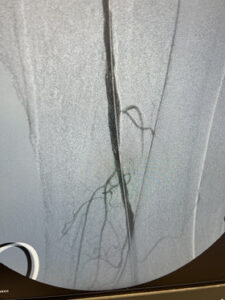

Ενδαγγειακή αποκατάσταση απόφραξης της ιγνυακής αρτηρίας

24 ωρη παραμονή στην κλινική

Ενδαγγειακή επαναγγείωση της ιγνυακής αρτηρίας

πλήρη ύφεση της συμπτωματολογίας

μετά απο 24 ώρες επιστροφή στην καθημερινότητα